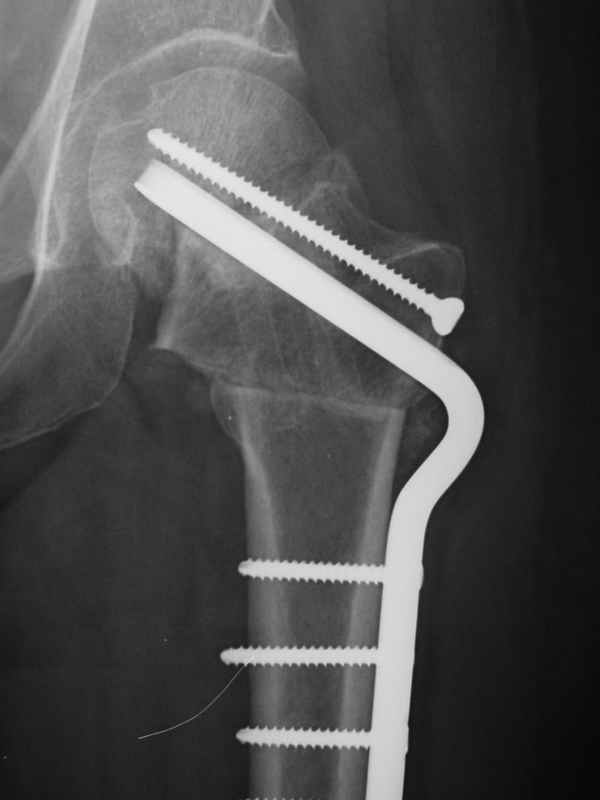

Stephen Kottmeier 17 Октябрь 2005, 21:05

friend

dhs will not correct improper biomechanical environment and may further compromise vascular

integrity consider establish vascular status via mri

and if viable follow with proximal valgus osteotomy

Отправитель: Peter Trafton 17 Октябрь 2005, 21:21

I think that this 31 yo deserves a try with valgus osteotomy, as so nicely illustrated by stephen kottmeier. However, I'd do it no matter what an MRI shows - thus why bother with the MRI? (What sort of data support MRI's ability to predict segmental collapse?)